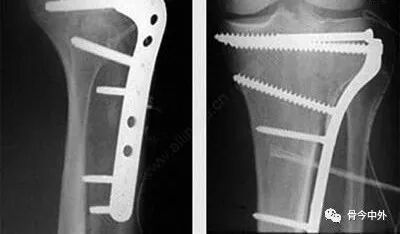

Clinical & Radiographic Imaging